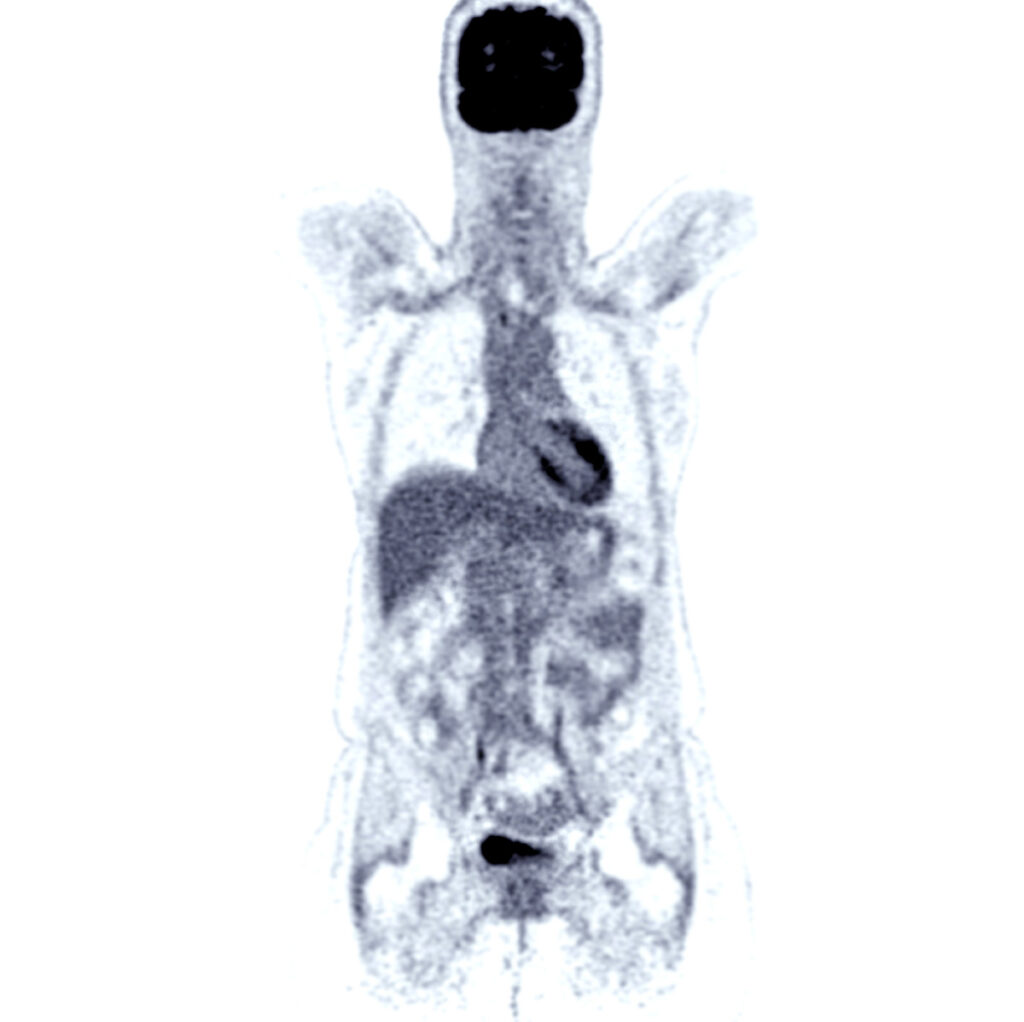

Cerianna (fluorine-18-fluorestradiol) is used with whole-body PET/CT imaging to differentiate estrogen receptors in tumors that have metastasized throughout the body. It is FDA approved and is performed at Imaging Healthcare Specialists in addition to biopsy.